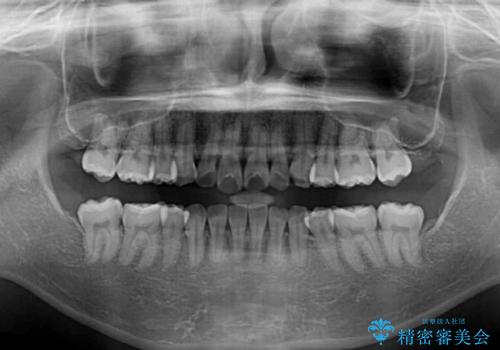

- 上下前歯の叢生を気にして来院された患者様です。

インビザラインでの治療を希望されていて、デコボコの程度が中等度であり、安価なパッケージにて対応可能と判断されたため、インビザライン・モデレートを用いて矯正治療を行うこととしました。